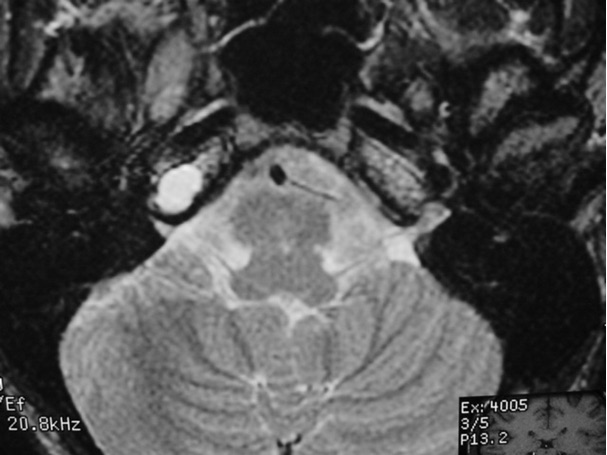

The petrous apex is a relatively inaccessible area that can occasionally harbor serious disease. Disease processes that usually cause symptoms are typically inflammatory or neoplastic in nature. Petrous apex lesions typically cause nonspecific symptoms such as headache, but as the lesion becomes more extensive, adjacent structures such as cranial nerves can become involved. A common early and specific sign of a petrous apex process is abducens palsy. Current imaging techniques can usually provide enough supplemental information to allow a focused plan of treatment. It is important to determine whether a petrous apex lesion can be observed or, if surgical treatment is required, whether a drainage or excision is required. There are various available surgical approaches to the petrous apex. The choice depends on the status of hearing function as well as the suspected pathology, which will dictate whether a drainage or excisional procedure is required.

- Summarize the types of pathology that can occur in the petrous apex, the imaging required, and proper interpretation of information so that a proper differential diagnosis can be formulated.